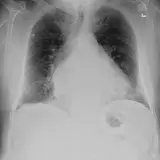

Over 2,100 interactive radiology cases, curated by radiologists for your level of training. Scroll, window, and view cases full screen — just like on PACS. Click linked findings in each writeup to jump straight to them on the image. Cases include sample reports, a focused discussion section, original illustrations, and videos.

PACSで期待されるツールを完備した完全インタラクティブな症例 — スクロール、ウィンドウ調整、ズーム、パン、計測、ROI、フルスクリーンモード。

重要な所見を症例画像上に直接ハイライトする豊富なアノテーション。症例解説内のリンクされた所見をクリックすると、スキャン上の正確な位置へジャンプできます。